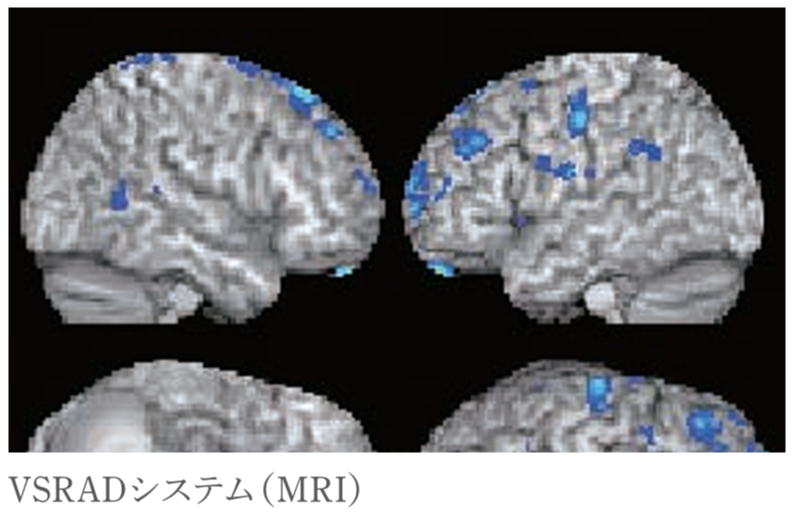

・VSRAD検査(MRI)

私たちの脳の中には記憶をつかさどる「海馬」という部分があり、それが萎縮しているかどうかを特別なソフト(VSRADシステム)を使用して調べます。